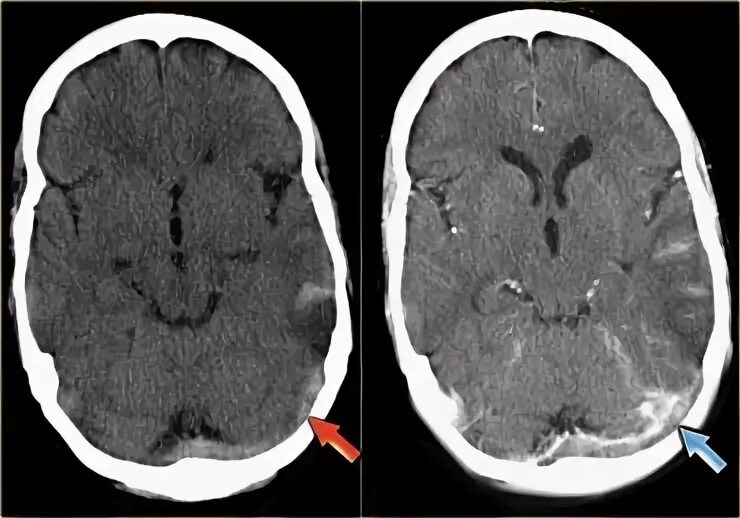

Синусы мозга мрт